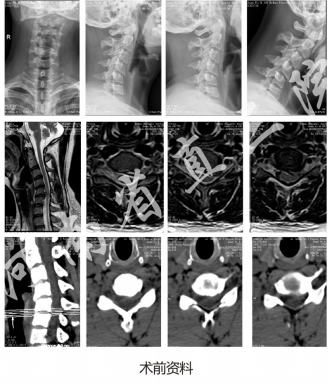

患者,男,30岁;

主诉:左上肢疼痛1月余

现病史:患者1月余前无明显诱因出现左上肢疼痛,以左肩部为重,影响睡眠,至当地医院行药物、针灸、理疗等保守治疗,效果不佳,为求脊柱微创诊治来我院,一般情况良好。

体格检查:步入病房,颈椎活动受限,左上肢感觉减退,左上肢肌力IV级,双侧肱二、三头肌腱反射活跃,左膝腱反射活跃,左侧Hoffmann征阳性,压头试验阳性,左侧臂丛神经牵拉试验阳性。

术前诊断:神经根型颈椎病(C5/6,脱出)

手术方案:UBE下C5/6开窗髓核摘除术